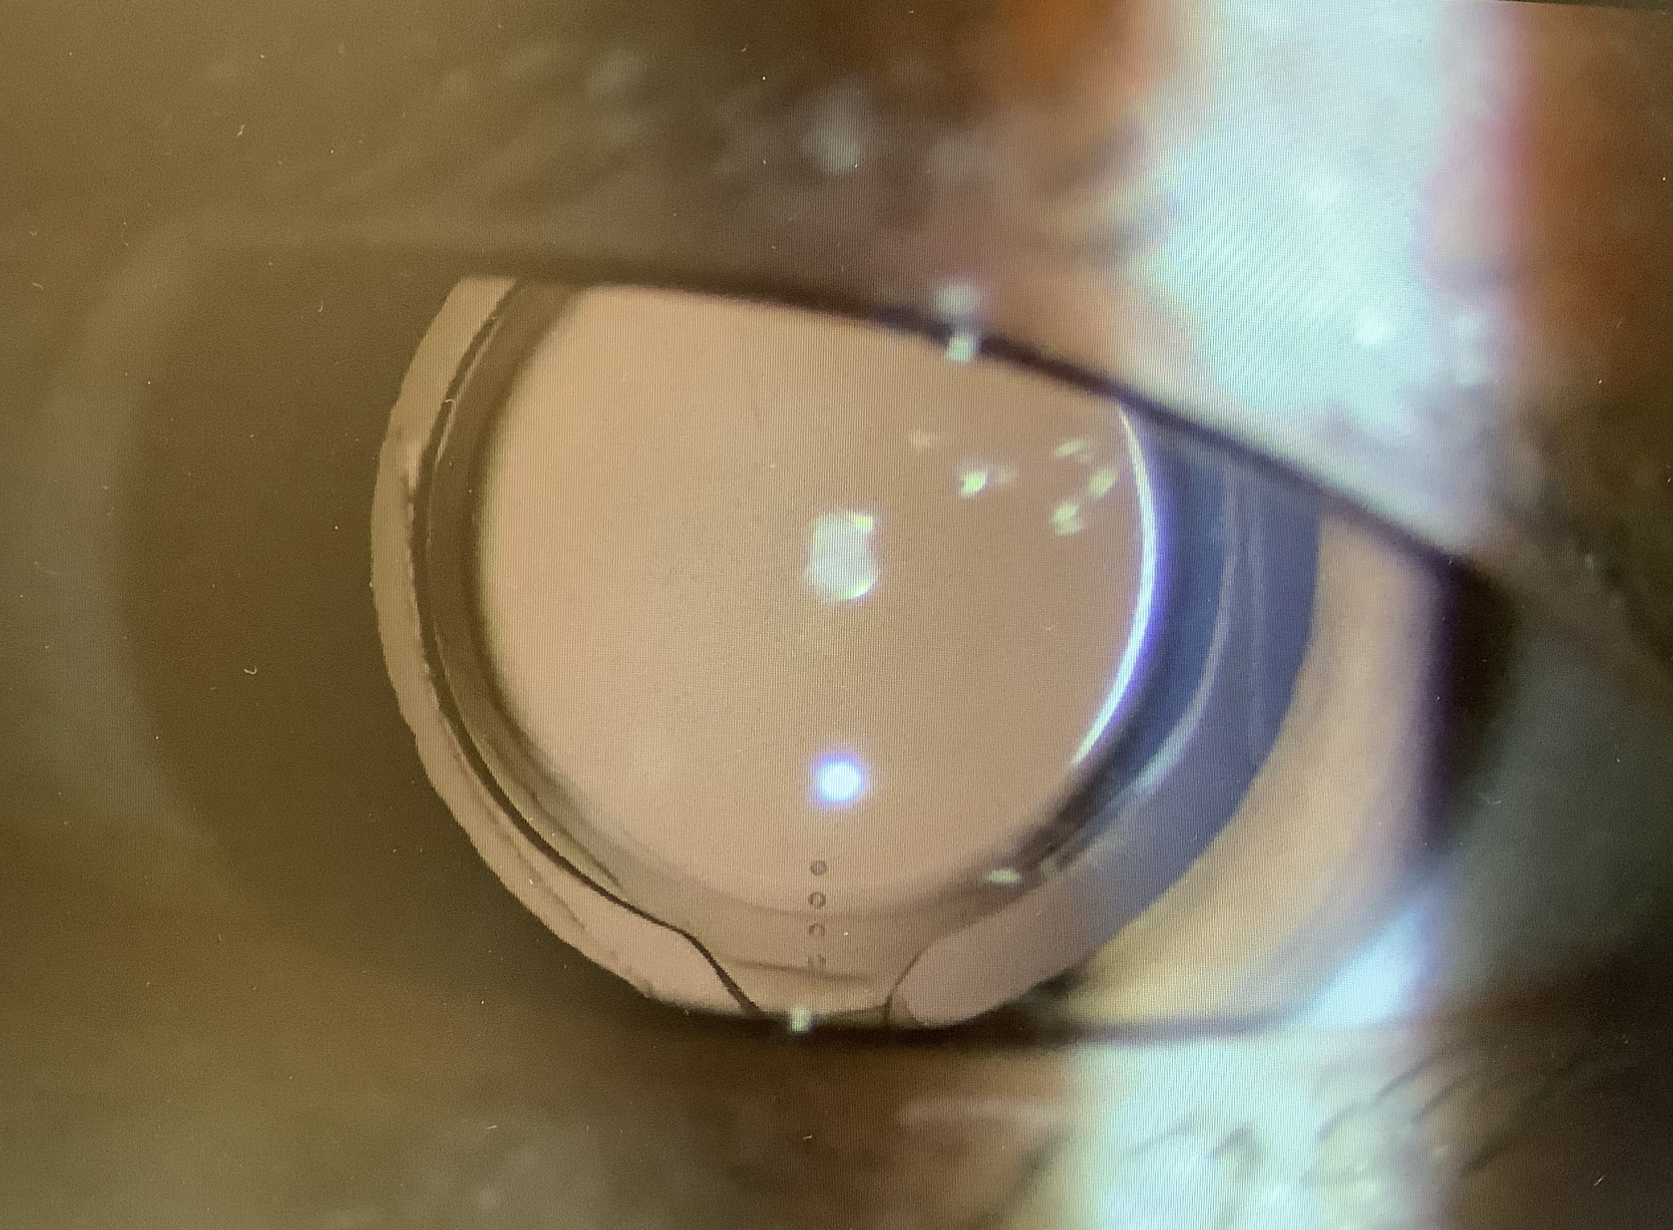

今日の外来では42歳の男性の方が『白内障の手術の後、右眼のみ夜間、遠くの光を見ると、二重に見えたり、扇状に光の線が見える』という症状でいらっしゃいました。眼の状態を見ると、レンズ自体はきれいに入っていて、視力(矯正)は1.0〜1.2と所見や検査結果上は明らかな問題はありませんでした。右眼はアイハンス、左眼はクラレオントーリックが入っているそうで、もしかすると、アイハンスの影響なのかなと思いました。単純な単焦点レンズでは問題なくとも、多焦点レンズやレンティス、アイハンスのような単純な単焦点レンズに比べて複雑な構造のレンズはほんの少しのレンズのズレや傾きが異常な光の見え方につながってしまう恐れがあると感じています(あくまでそう感じているだけですが、“コマ収差”が生じやすくなってしまうのかなと思っています)。

ただ、仮にアイハンスのレンズの入り方が原因だとして、不快な症状を改善するために、アイハンスのままレンズの位置を調整することは現実的に難しい可能性が高く、アイハンスを諦めて単純な単焦点レンズへ入れ換えることがどこまでメリットが得られ、デメリットが出るかをよく考えて治療を決めないといけないと思いました。